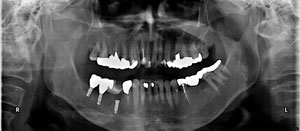

M.Y‚³‚ñ@69Π —«@Ž©‰c @Žèp“ú@

‚Q‚O‚O‚X”N@‚QŒŽ‚Q‚S“úi‰Îj  ㉺Š{ƒm[ƒxƒ‹ƒKƒCƒhŽg—p@Ö¬“à’ÁÖ@•¹—p@

@@@ãŠ{@All on ‚P‚O ‘¦Žž‰×d@@Rpl Tapered Np ‚P‚O mm(‚Q–{) @@@@@@   Rpl Tapered Groovy Np ‚P‚U mm(‚Q–{)   @ Rpl Tapered Groovy Rp ‚P‚R mm

@@@@@@@@@@@@@@@@@@@@@Rpl Tapered Groovy Rp ‚P‚U mm    @@     Rpl Tapered Wp ‚P‚U mm @@  @@@         Rpl Tapered ‚UD‚OƒÓ   ‚P‚O mm

@@@@@@@@@@@@@@@@@@@@@Nobel-Speedy Groovy Rp ‚WD‚T mm         Nobel-Speedy Shorty Rp

@@@‰ºŠ{@All on ‚U  ‘¦Žž‰×d@ @Rpl Tapered Np ‚P‚R mm  @@  Rpl Tapered Groovy Rp  ‚W mm @@@ @Rpl Tapered Groovy Rp ‚P‚O mm(‚Q)

@@@@@@@@@@@@@@@@@@@  @Rpl Tapered Rp ‚P‚R mm         Rpl Tapered Groovy Np ‚P‚R mm